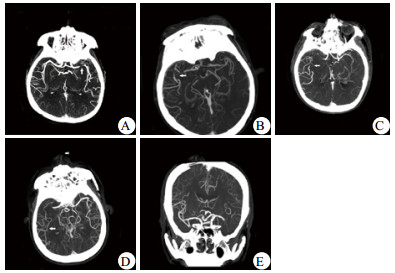

1.2 方法共有153例急性脑梗死患者完成绿色通道治疗,本研究入选标准为其中头颅CTA显示颈内动脉(internal carotid artery, ICA)或大脑中动脉(middle cerebral artery, MCA)梗死者。排除标准为既往存在严重的心肺不全或遗留神经功能缺失。按该标准,共有94例患者纳入研究。本研究观测终点为再通治疗后30 d,近期预后改善指符合以下全部标准:期间患者存活、未发生症状性脑出血,并且30 d NIHSS评分较治疗前提升 > 4分[9-10],否则认为近期预后不良。研究患者的相关临床因素,分析引发不良预后的危险因素。纳入的临床因素包括年龄、性别、既往史(房颤、高血压、糖尿病)、治疗时间、治疗方式、梗死部位、侧支循环状况。部分因素的定义区分如下:年龄高低以≥70岁或 < 70岁区分;治疗时间指从症状出现至首次进行溶栓或介入治疗的时间,时间早晚以 < 4 h或≥4 h区分;治疗方式分为仅溶栓、仅介入、溶栓衔接介入治疗;梗死部位指闭塞或狭窄部位发生在ICA或MCA;侧支循环状况参照软脑膜侧支评分(pial collateral score)[11]:1分-闭塞血管的远端部分有侧支循环重建;2分-侧支重建血管出现在与闭塞血管相邻的近端部分;3分-侧支重建血管出现在与闭塞血管相邻的远端部分;4分-侧支重建血管出现在闭塞血管两段远端;5分-闭塞血管支配区无或仅有较少的侧支血管重建。以1~2分为侧支循环良好,3~5分为侧支循环不良[10], 见图 1。

|

| A: 1分,左侧大脑中动脉M1闭塞,M1远端重建;B: 2分,右侧大脑中动脉M1闭塞,M2近端重建;C: 3分,右侧大脑中动脉M1闭塞,M2远端重建;D:4分,右侧大脑中动脉M1闭塞,M3分支重建;E: 5分,左侧大脑中动脉M1闭塞,其支配区仅有少量血管重建。箭头示侧支重建血管出现位置 图 1 软脑膜侧支评分 Figure 1 Pial collateral score |

|

|